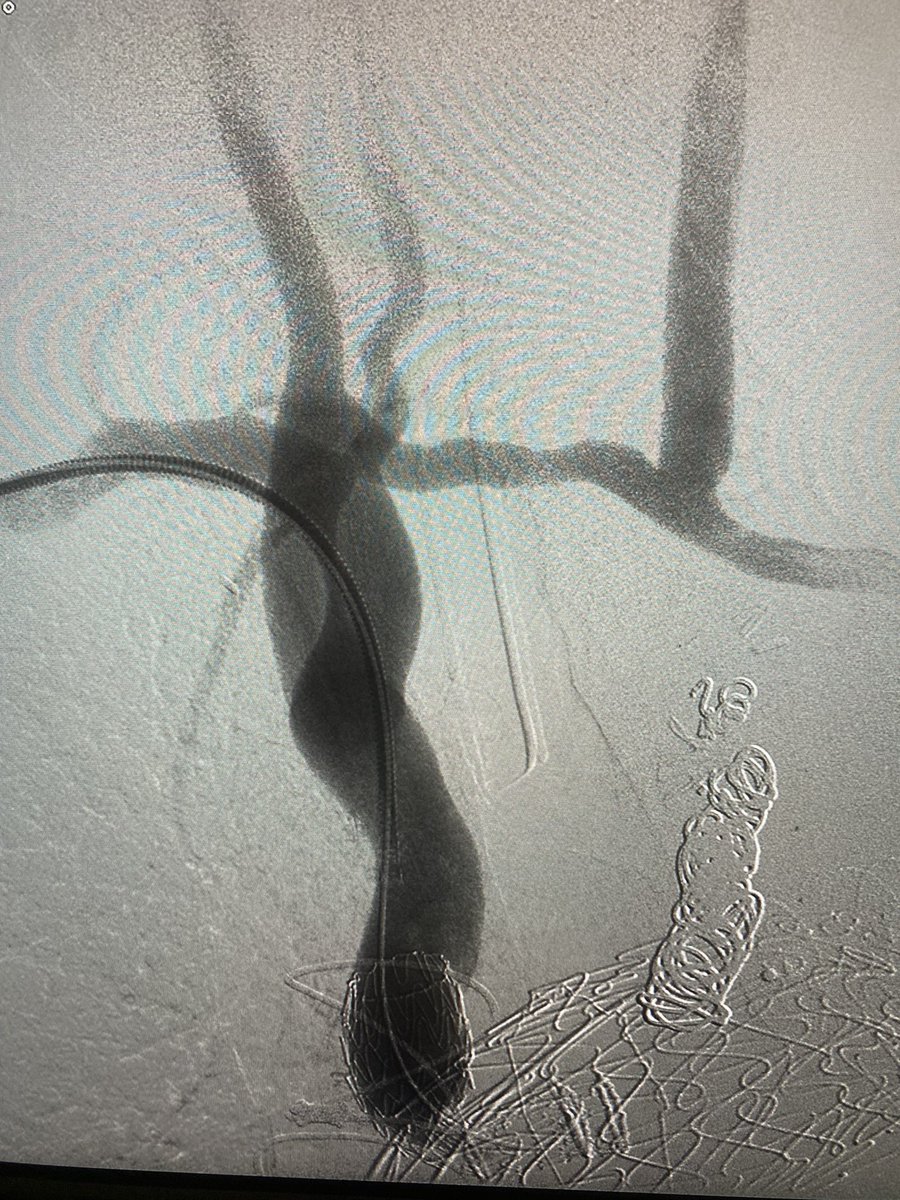

@Kniery_Bird @LucynaPrice @DanHan @JFMVasc @ReidRavin This pt had a ruptured juxtarenal AAA. We keep a cookie-cutter z-fen on the shelf that wouldn’t have worked in this case. He was a thin 70 y/o with no known prohibitive risk factors, so we felt open repair was most ideal. Snorkel technique is an option, but less definitive.

@Kniery_Bird @LucynaPrice @DanHan @JFMVasc @ReidRavin We went RP. We had a balloon in from the Rt femoral in the event we needed it. He also had a large Rt CIA to exclude, so we planned to sew to the Rt CFA. Clamp was suprarenal. Always ID the left renal a and v, as well as the renolumbar vein that needs to be ligated and divided.